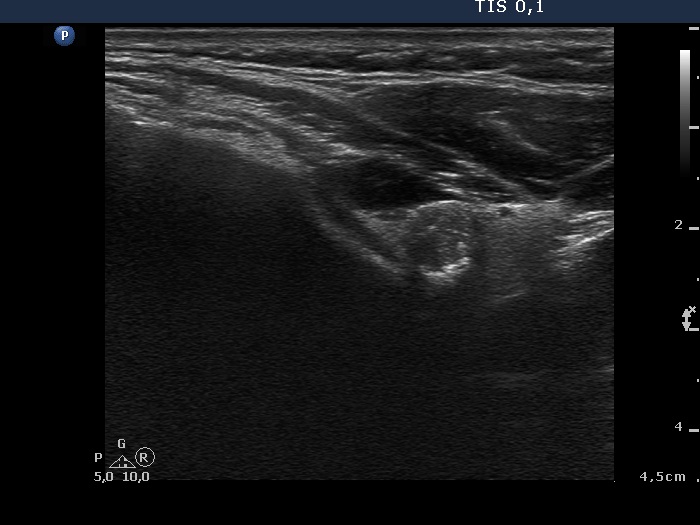

Ultrasonography: a large lesion composed of multiple moderately hypoechogenic and hyperechogenic nodules occupies almost the entire right lobe. There was a small hypoechogenic nodule in the upper pole while a cystic nodule in the central part of the left lobe. The former presented coarse and microcalcifications, too. The vascularization was not specific.

Cytology was performed form the nodule in the upper pole of the left lobe and resulted in papillary cancer.